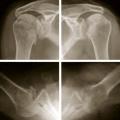

Luxation gléno-humérale postérieure bilatérale

LESIONS PERI-ARTICULAIRES

LESIONS LIGAMENTAIRES